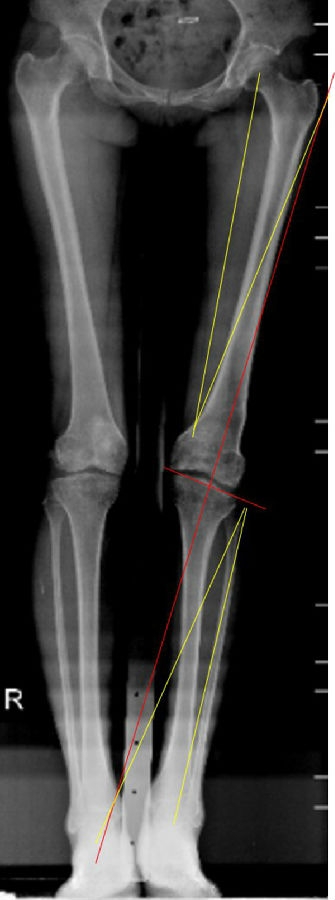

术前X线片

术前X线显示:

胫骨近端内侧角(MPTA):100°

股骨远端外侧角(LDFA):102°

关节线夹角(JLCA):

股骨远端后倾角(PDFA):85°

胫骨近端后倾角(PPTA):83°